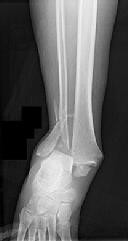

Figures 1 and 2 are the radiographs of a 68-year-old woman who comes to the emergency department after stepping into a hole and twisting her ankle. She is complaining of isolated ankle pain and is unable to bear weight.

After closed manipulative reduction and splint placement, she is scheduled for operative treatment. The stability of the syndesmosis should be evaluated after